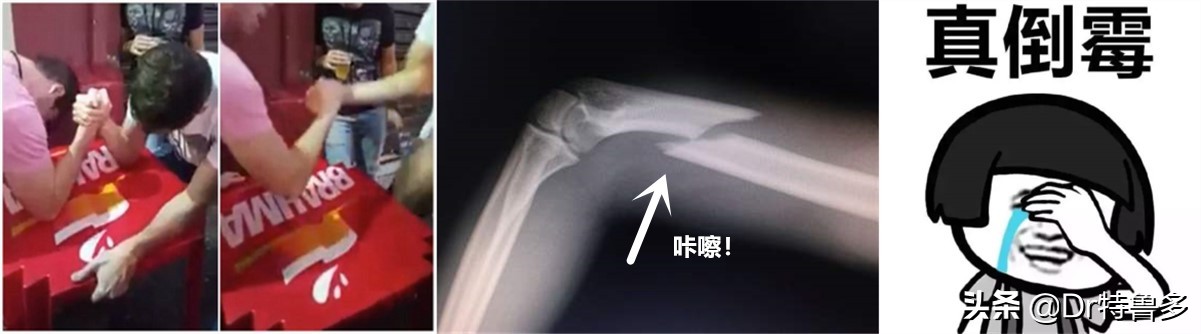

骨折,已经够倒霉了!石膏、支具非手术治疗也好,钢板螺钉手术也罢,痛苦忍受了,钱也花了不少,最悲催的事情还是发生了——骨折,长不上!

目前,医学界关于“骨折不愈合”的共识是:骨折发生后9个月,并且连续有3个月在X线片上看不到骨折愈合的趋势——符合这种状况的,基本可以认定,不是时间不够,的确是骨折愈合出了问题!